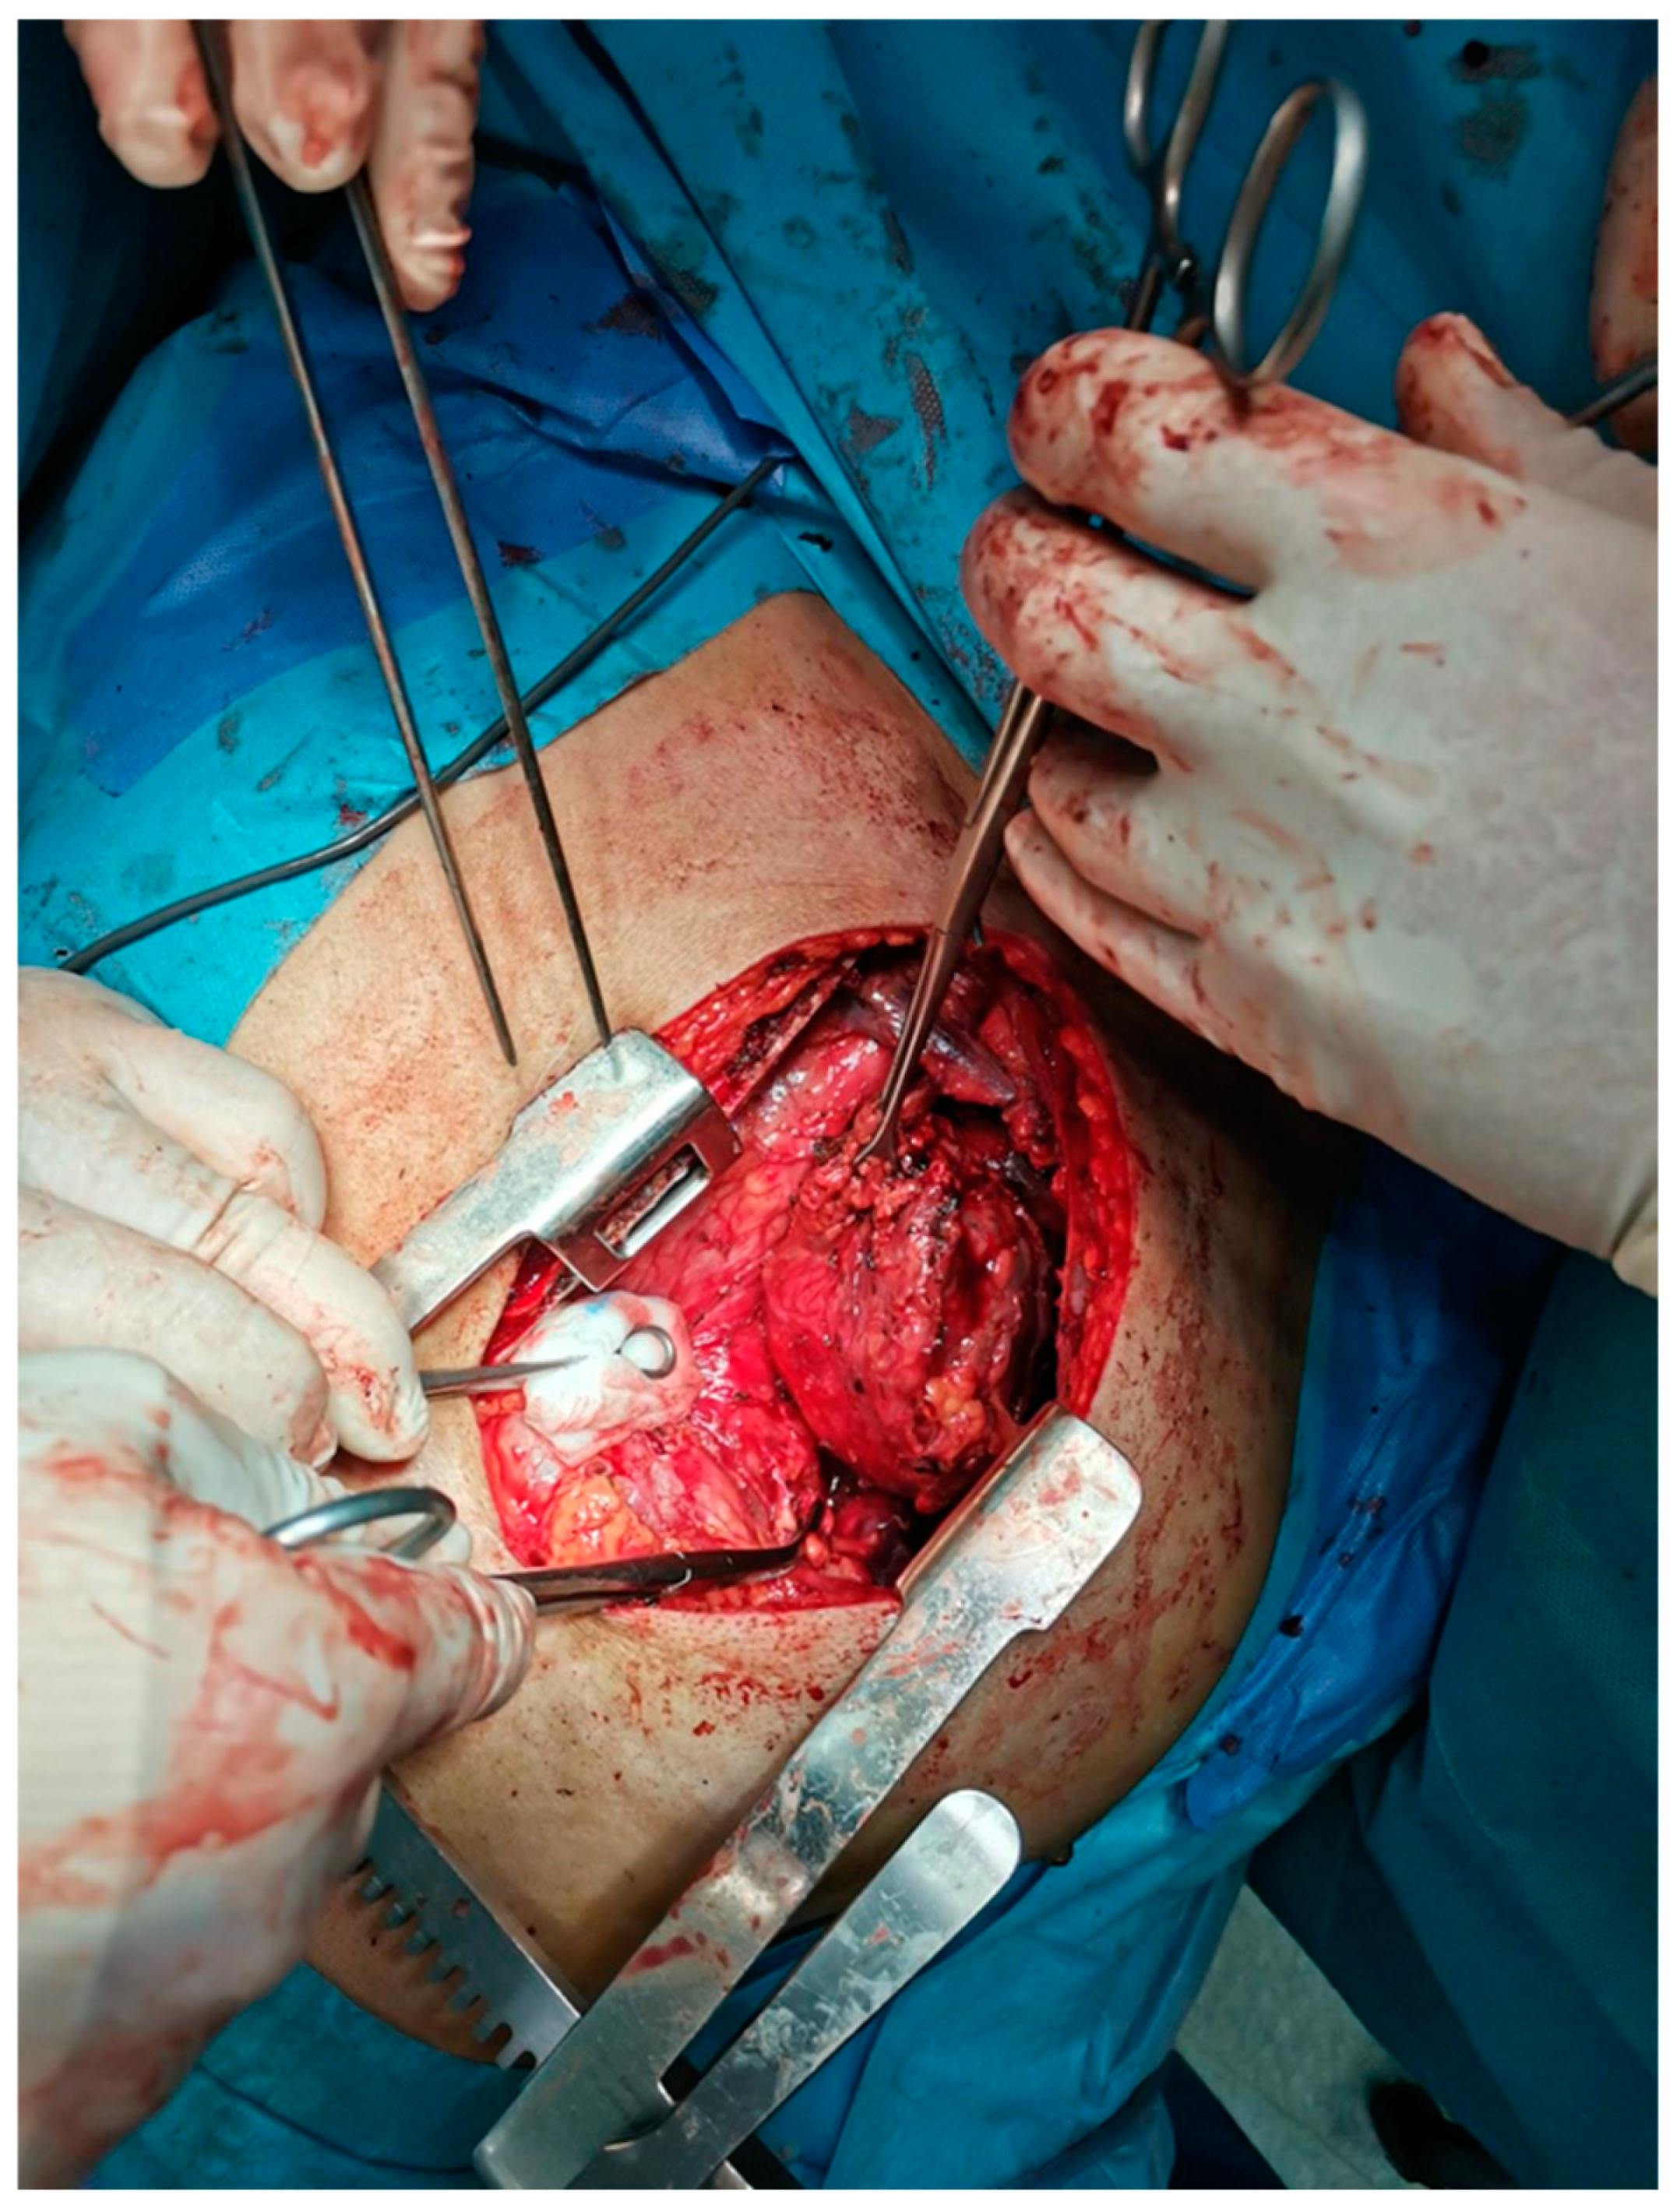

- Chaudhry, I.U.; Rahhal, M.; Khurshid, I.; Mutairi, H. Radical surgical resection for giant primary mediastinal endodermal sinus tumour with pulmonary metastasis after chemotherapy: Can be curative. BMJ Case Rep. 2014, 2014, bcr2014204662. [Google Scholar] [CrossRef]

- Wright, C.D.; Kesler, K.A. Surgical techniques and outcomes for primary nonseminomatous germ cell tumors. Chest Surg. Clin. N. Am. 2002, 12, 707–715. [Google Scholar] [CrossRef]

- Walsh, G.L.; Taylor, G.D.; Nesbitt, J.C.; Amato, R.J. Intensive chemotherapy and radical resections for primary nonseminomatous mediastinal germ cell tumors. Ann. Thorac. Surg. 2000, 69, 337–343. [Google Scholar] [CrossRef] [PubMed]